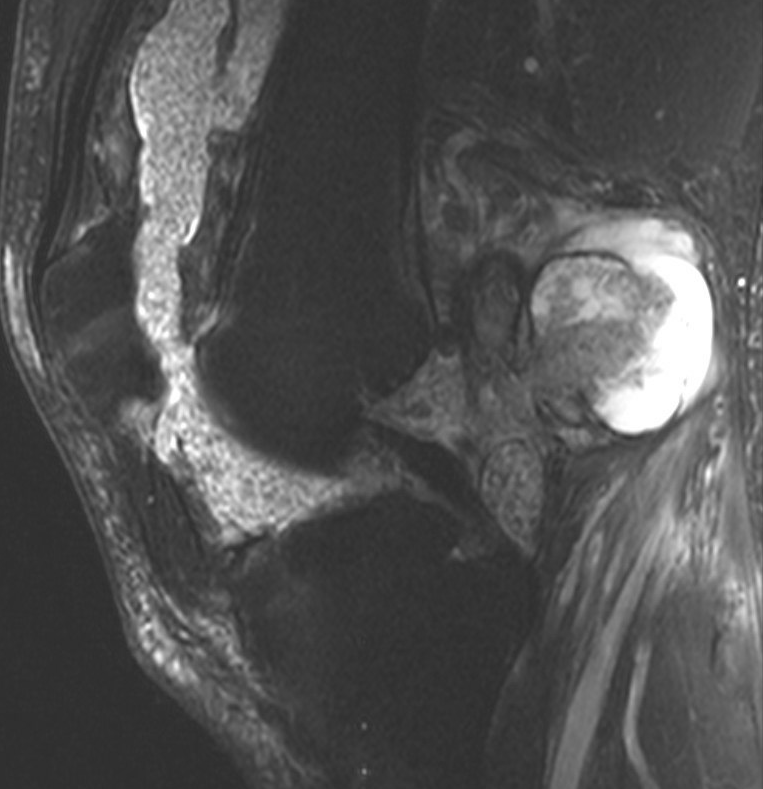

MRI

Synovial Proliferation

Soft tissue lesions same signal intensity as cartilage

Synovial chondromatosis

Synovial osteochondromatosis